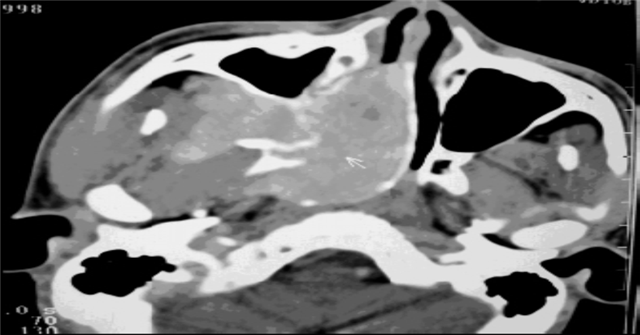

图3、CT 横断位: I肿瘤鼻腔, 骨质无破坏, 增强病灶明显强化(图片来源于医院影像中心)

目前主要通过鼻内镜或者电子鼻咽检查予以初步诊断,最终依赖于鼻咽部CT和MRI来术前诊断。